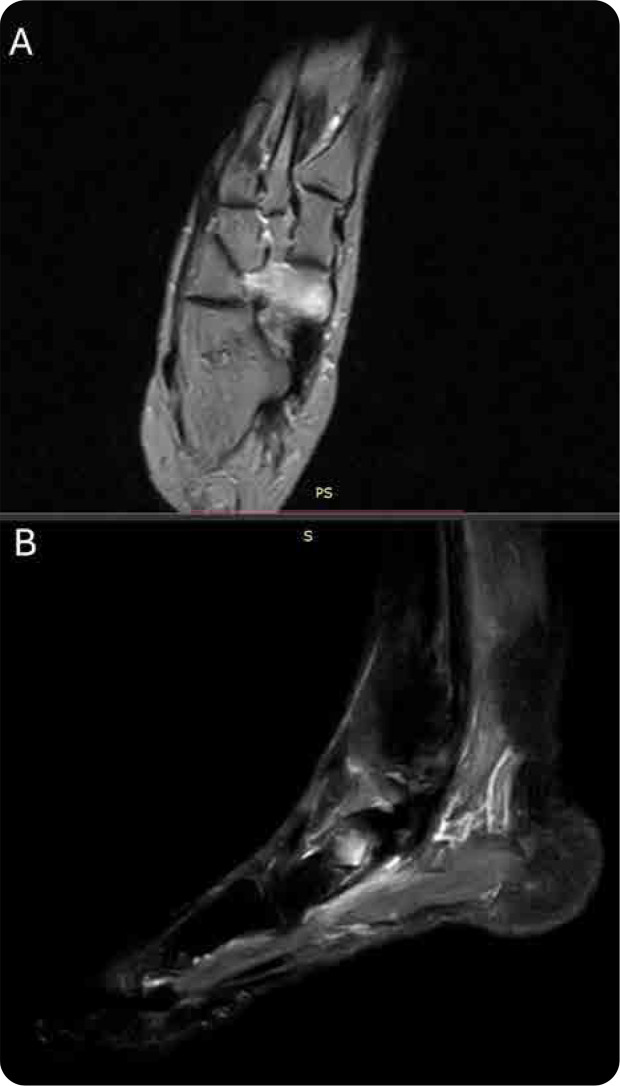

We report the case of a 50-year-old female smoker presenting with isolated algodystrophy of the navicular bone and concurrent nailfold videocapillaroscopy (NVC) abnormalities. This observation raises the possibility of an association between microvascular alterations and the etiopathogenesis of algodystrophy. NVC revealed enlarged loops, tortuosity, pericapillary oedema, and microhaemorrhages, findings indicative of impaired microcirculation. Magnetic resonance imaging (MRI) of the foot demonstrated bone marrow oedema consistent with algodystrophy. The patient underwent intramuscular treatment with neridronate, which resulted in full symptomatic remission and radiological resolution at three months. This case highlights the potential role of microvascular dysfunction in algodystrophy and suggests that NVC may serve as a valuable diagnostic tool in patients with unexplained regional pain syndromes. Future studies are required to establish a definitive causal relationship.